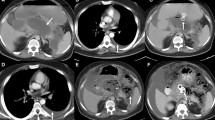

Table 2 summarizes CT radiation dose indices for the participating sites and CT protocols. institution and across different institutions for the same protocols (p < 0.001) (Fig. 3). Table 3 presents data on significantly different total iodine load and iodine delivery rates at different CT protocols across the 43 participating sites (p = 0.001). There was no significant difference between radiation doses for non-contrast (CTDIvol 24 [16–30] mGy; DLP 633 [414–702] mGy·cm) and post-contrast phases (22 [19–27] mGy; 648 [392–694] mGy·cm) (p = 0.142). Most sites with bolus tracking for chest and AP CT had lower CTDIvol than the sites with fixed scan delays (p < 0.001). Regardless of the CT vendor and model, body size, and scan protocols, most CT examinations were performed at 120 kV or 140 kV.

There was no significant correlation between patients’ size (BMI) and ICM or radiation doses for any of the six CT protocols included in our study (r2 ≤ − 0.1 to 0.1). When comparing median DLP and CTDIvol levels between different patient sizes, we noticed no significant difference between radiation doses for underweight-normal and overweight-obese patients (p > 0.05). Furthermore, in terms of total iodine load comparison in terms of different patient sizes, underweight-normal BMI patients received significantly lower total iodine load (p < 0.05) (Fig. 4). Regardless of the CT protocols, exams with bolus tracking and test bolus timing of scan delay had lower radiation doses (CTDIvol) as compared to the fixed scan delay (p < 0.001).

We report a lack of size-based differences in radiation doses across most CECT protocols. There were up to 10-fold inter-institution variations in radiation doses and total iodine load, which could be attributed to variations in scanner technologies and local practices. Furthermore, we employed a stratified analysis of doses by the scanner technology and found out that there was no difference with 4-fold interinstitutional variations in radiation doses among sites with both < 64-detector-row scanners and ≥ 64-detector row scanners. Multiple prior studies have reported on major variations in radiation doses in international settings with limited (such as in our study) and large clinical datasets [1, 6]. For example, Rebecca et al [1] reported on a large international registry of CT radiation doses from over 2 million CT examinations in adult patients across 151 institutions from seven countries. They documented major variations in radiation doses across countries despite controlling for patients, institutional, and scanner characteristics. The authors attributed such variations to the choice of technical parameters used during CT image acquisition [1].

On the upside, a few sites that used weight-based ICM dosage had expected variations in radiation doses. Other sites could emulate such protocols to improve their practices. Likewise, sites that used bolus tracking or timing bolus, had lower ICM usage and radiation doses than sites with fixed ICM volume. Most sites used bolus tracking or timing bolus techniques to trigger scanning for CTPE, as opposed to head CTA and biphasic liver protocol CT where fixed scan delay was frequent. The latter can result in suboptimal contrast enhancement and require either additional scan phases or repeat acquisition if the initial scan timing yields an insufficient contrast enhancement. Another aspect of our study pertains to the size-based ICM usage at most participating sites, which resulted in expected differences in total iodine load between patients of different body habitus for all CT protocols. However, up to 10-fold variation in iodine load for the same CT protocol from different sites suggests a lack of standardization with at least some sites using higher and others using much lower ICM protocols.